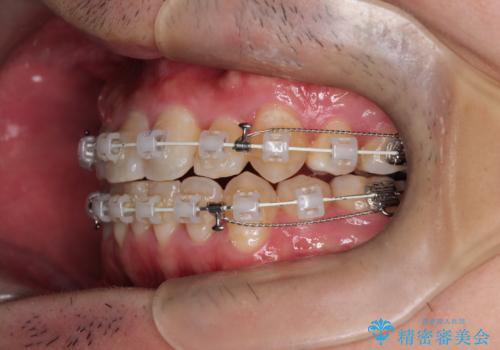

【重度叢生ワイヤー矯正】きれいな歯並びにしたい

- 審美装置

- きれいな歯並びにしたいとの希望を持って来院された患者様です。

上下左右小臼歯を抜歯する治療計画を立て審美装置にて治療を行いました。

骨格的3級傾向もあり、咬合関係を仕上げるのに時間がかかりましたが、患者様には大変満足していただけました。

難しいケースでしたが、矯正用アンカースクリューを用いながら、臼歯関係もきれいに仕上げることができました。